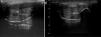

An ultrasound study of both lesions was undertaken with a linear 14MHz probe. The first lesion showed marked focal thickening of the subcutaneous cell tissue of the shaft of the penis, with no collections or foreign bodies detectable in the ultrasound throughout its thickness (Fig. 3a). No abnormalities were observed in the corpora cavernosa or the corpus spongiosum. In the second lesion, a well-defined hyperechogenic nodule measuring 10×12mm in diameter was observed with a posterior acoustic shadow (Fig. 3b). In addition, bilateral hyperechogenic swollen inguinal lymph nodes with no defined fatty hila could be observed, probably related to lymphatic drainage of foreign material.

An exhaustive medical history is essential for diagnosis, as the patient may omit part of the prior history due to fear or shame.3 Differential diagnosis should include infectious processes such as abscesses, canker sores, thrombosis of the dorsal vein of the penis, and tumors.7 Ultrasound, which is a widely available and inexpensive technique, can be very useful for differential diagnosis. This imaging technique can also determine the involvement of structures such as the corpora cavernosa and regional lymph nodes, as well as detect the formation of abscesses or fistulas. Furthermore, it can help identify the type of filler material, as specific echographic patterns have been described for some of these.8–10 For example, in the second image, the so called snow storm pattern is observed, where a hyperechogenic region has a posterior acoustic shadow. This pattern is typical in nonabsorbable filler materials such as silicone oil, pure silicone,10 and, in our case, liquid paraffin.